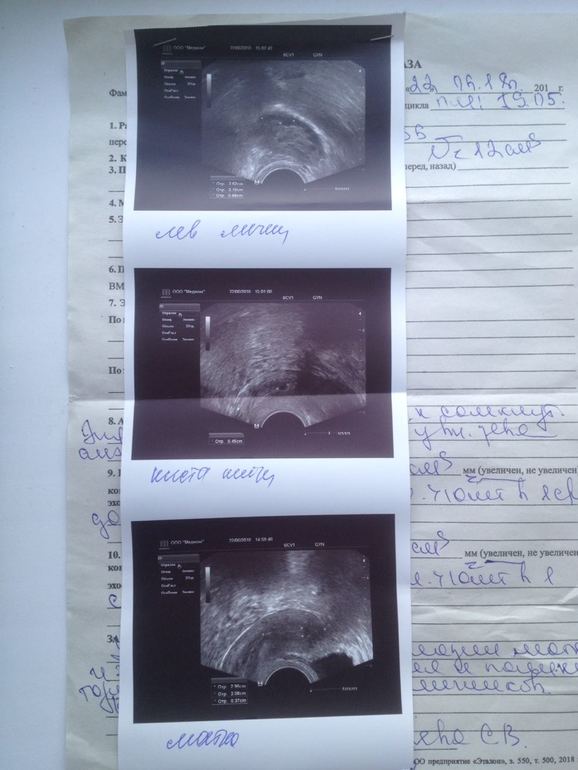

Нет месячных уже месяц, тесты отрицательные, Пошла на прием к гинекологу, взяла мазки, отправила на УЗИ, поставили диагноз гипоплазия матки и эндометрия, увеличение и поликистоз обоих яичников, врач сказала, что с таким диагнозом о детях могу и не мечтать, пока не вылечусь. Назначила мне прогестерон колоть чтобы вызвать месячные и сдать анализы на половые гормоны, их по 4, в двух циклах, стоимость их в районе двух тысяч рублей каждый, 16 тысяч в сумме, только за гормоны. Стоит ли их сдавать?! Кому ставили такой диагноз, кто чем лечился?